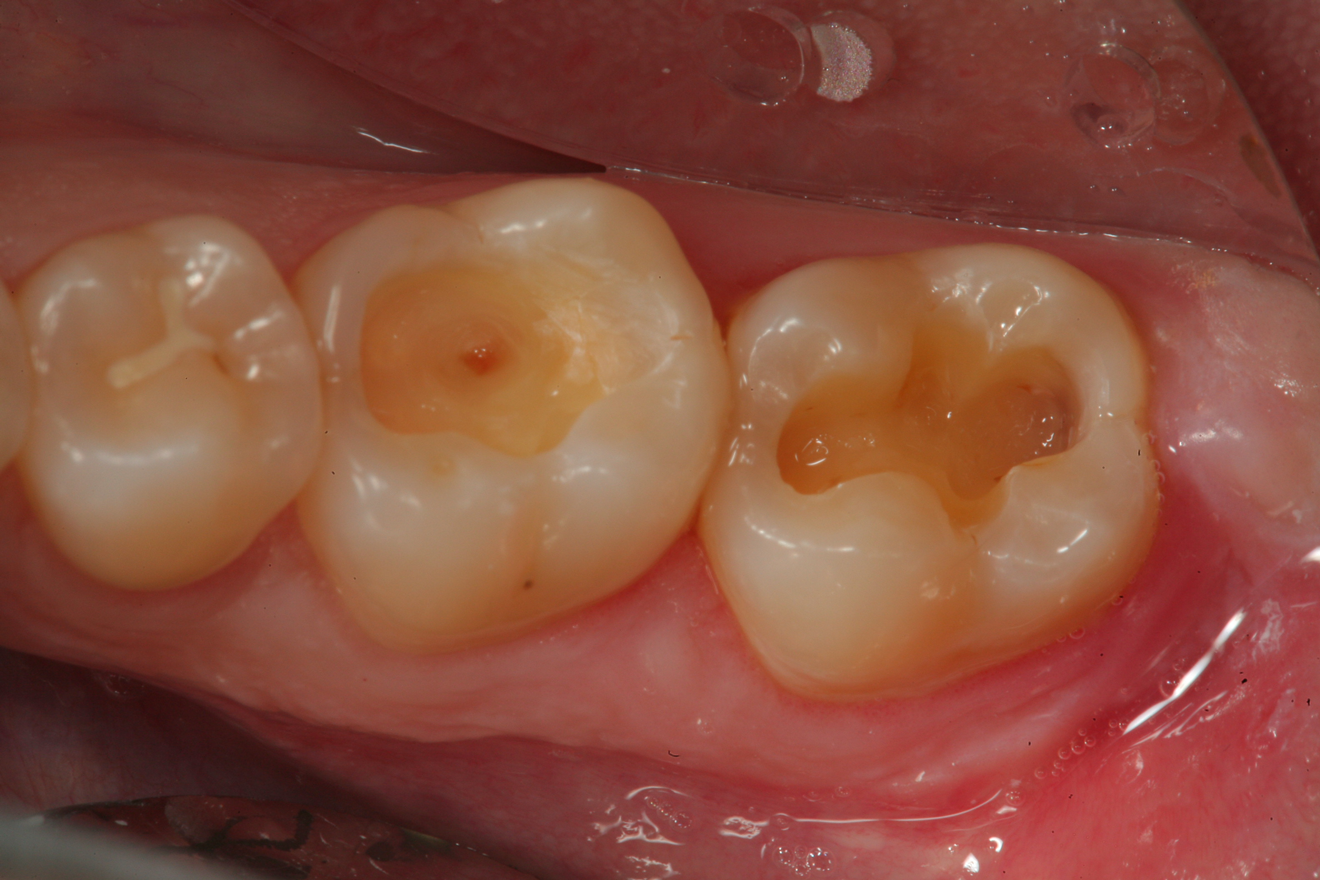

A 32 year-old female patientpresented with old composite restorations in tooth Nos. 18 and 19 that exhibited marginal leakage with potential for recurrent decay (Figure 10).  After excavation, both teeth had deep decay beyond the extent of the restorative material, with tooth No. 19 having a "pinpoint" carious exposure of the pulp chamber (Figure 11).  Figure 12 is a diagrammatic representation of the therapeutics that were used after removal of infected dentin and control of the bleeding from the pulp exposure.  A pulp protectant/liner that is indicated for use on a direct pulp exposure (TheraCal LC, Bisco Dental Products) was placed directly on the exposed area and light cured.  Both preparations were then filled with a bioactive dentin replacement (TheraBase, Bisco Dental Products) to a point just apical to the dentoenamel junction (Figure 13).  Selective etch protocol was then used, etching the enamel (Select Etch HV, Bisco Dental Products) for 15 seconds (Figure 14), then rinsing with water and drying.  Next, a universal bonding agent (All-Bond Universal, Bisco Dental Products) was placed, air thinned, and light cured (Figure 15).  Figure 16 is an occlusal view of the completed restorations.  Both teeth are planned to be followed and radiographed periodically to ensure that the pulps are responding favorably.

Fig 10. A preoperative occlusal view of tooth Nos. 18 and 19 with composite restorations that are exhibiting marginal breakdown.

Figure 10

Fig 11. After removal of the existing restorations and associated recurrent decay, both cavities are very deep and there is a pinpoint pulpal exposure on tooth No. 19.

Figure 11